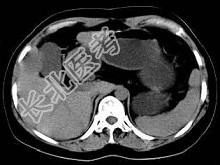

- 单项选择题根据所提供的图像,最可能的诊断为 ( )

A、肝平滑肌瘤

B、肝癌

C、肝血管瘤

D、局灶性结节增生

E、肝囊肿